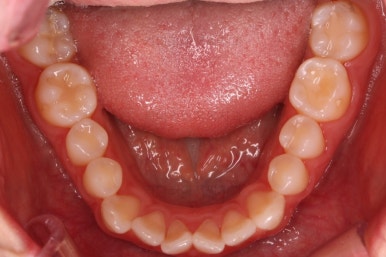

부산나비앞니교정 키다리아저씨치과에서 치료를 한 지 3개월째의 모습입니다.

굉장히 많이 가지런해 진 것을 볼 수 있어요.

그래도 여전히 나비앞니의 느낌이 남아있어서 미세한 조절을 더 하고 마무리를 하기로 했습니다.